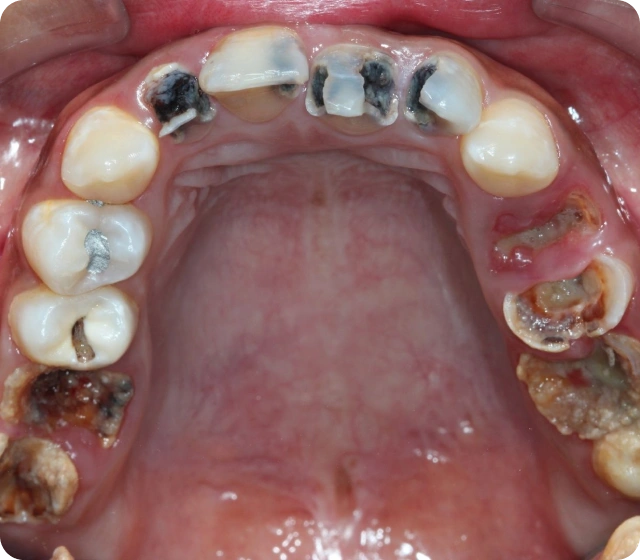

Karies ist eine weit verbreitete Zahnkrankheit, die durch das Zusammenspiel von Bakterien und Zuckern entsteht. Diese Mikroben produzieren Säuren, die den Zahnschmelz angreifen und dessen Struktur schädigen. Im Anfangsstadium kann sich Karies durch Flecken auf den Zähnen bemerkbar machen, die auf beginnende Karies hindeuten. Wenn sie nicht behandelt wird, breitet sich die Erkrankung in tiefere Schichten, wie das Dentin, aus und führt zu schmerzhaften Löchern. In solchen Fällen ist ein Zahnarzt gefragt, um die kariesbehandelte Stelle zu reinigen und die Zahnsubstanz mit einer Füllung, oft aus Kunststoff oder Komposit, zu ersetzen. Regelmäßige Zahnarztbesuche und eine gute Mundhygiene sind entscheidend, um Karies zu verhindern und die Zähne gesund zu halten.

Karies entsteht durch das Zusammenspiel von Bakterien und Zucker, die in der Mundhöhle Säuren produzieren. Diese Säuren greifen den Zahnschmelz an und führen zu einer Demineralisierung der Zahnsubstanz. Zu Beginn können sich flecken auf den Zähnen zeigen, was auf beginnenden Karies hindeutet. Ohne regelmäßige Zahnpflege und Besuche beim Zahnarzt schreitet die Krankheit voran und kann bis ins Dentin vordringen, wo schmerzen und ein Loch im Zahn entstehen können. In fortgeschrittenen Stadien ist eine Kariesbehandlung notwendig, oft durch das Bohren und Entfernen kariöser Bereiche, gefolgt von einer Zahnfüllung aus Kunststoff oder Komposit. Die Anwendung von Fluorid kann helfen, gesunde Zähne zu erhalten und beginnende Karies zu stoppen.

Karies entsteht durch das Zusammenspiel von Bakterien und Säuren, die den Zahnschmelz angreifen. Zu den häufigsten Symptomen von Karies gehören Schmerzen im betroffenen Zahn, besonders bei süßen oder heißen Speisen. In den frühen Stadien kann es zu einem lochen Gefühl im Zahn kommen. Wenn die Karies fortgeschritten ist, sind Zahnsubstanz und tiefer liegende Gewebe betroffen, was häufig eine Kariesbehandlung durch den Zahnarzt erforderlich macht. Bei regelmäßigen Zahnarztbesuchen können beginnende Karies frühzeitig erkannt und behandelt werden, oft durch eine Zahnfüllung aus Kunststoff oder eine Kariesinfiltration.